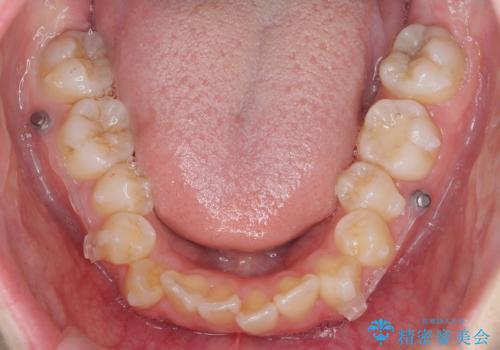

下の八重歯 歯を抜かずに インビザライン治療

- 歯並びのがたつきを主訴に来院。

抜歯してワイヤー矯正という選択肢も提案しましたが、マウスピース矯正で、歯を抜かずに並べてほしいとのことでした。

スペースを確保するために、歯をわずかに削る処置、奥歯を後ろに下げる処置(インプラント矯正)を行っています。

途中患者様のご都合で治療を中断していたため、長くかかっていますが、実質2年程度で終わる内容でした。